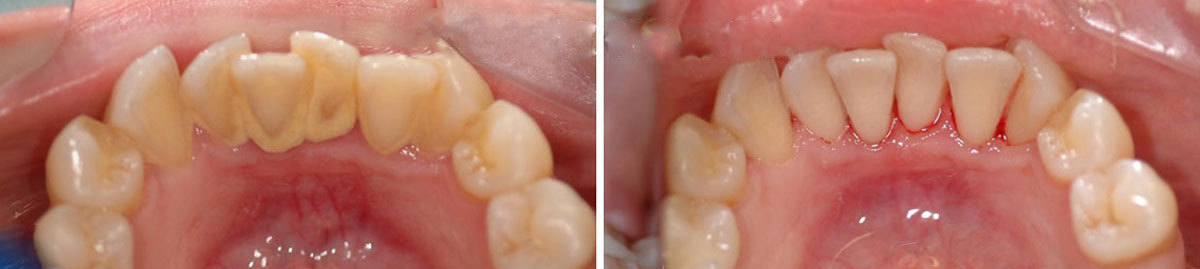

Зубной камень: фото до и после

Зубной камень — это затвердевший налет, который не был удален во время домашних процедур по уходу за полостью рта. Кроме эстетических проблем эти отложения способны доставить массу других неприятностей: они провоцируют различные стоматологические заболевания (кариес, гингивит, пародонтит) и в дальнейшем могут стать причиной потери зубов.